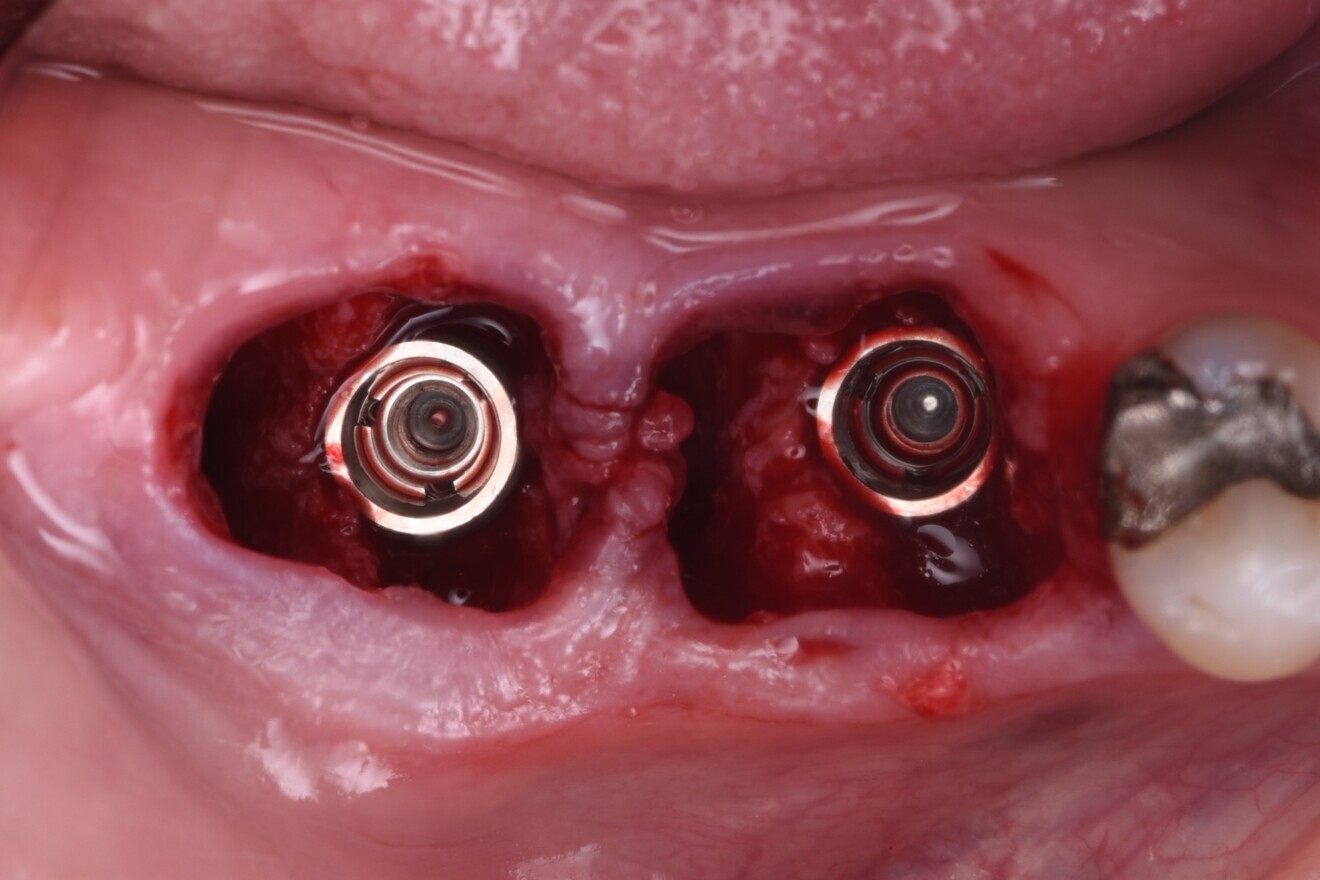

Fig. 2: Pre-op radiograph.

A 57-year-old male patient presented by referral with two failing molars, teeth #46 and 47. The patient had a clear medical history, and both molars exhibited extensive caries and restoration (Figs. 1–6).

The failing teeth were sectioned and extracted atraumatically to preserve the surrounding bone (Fig. 7). The sockets were thoroughly debrided using Lucas curettes to remove any residual infection or granulation tissue (Fig. 8).

Fig. 8: Sockets thoroughly debrided.